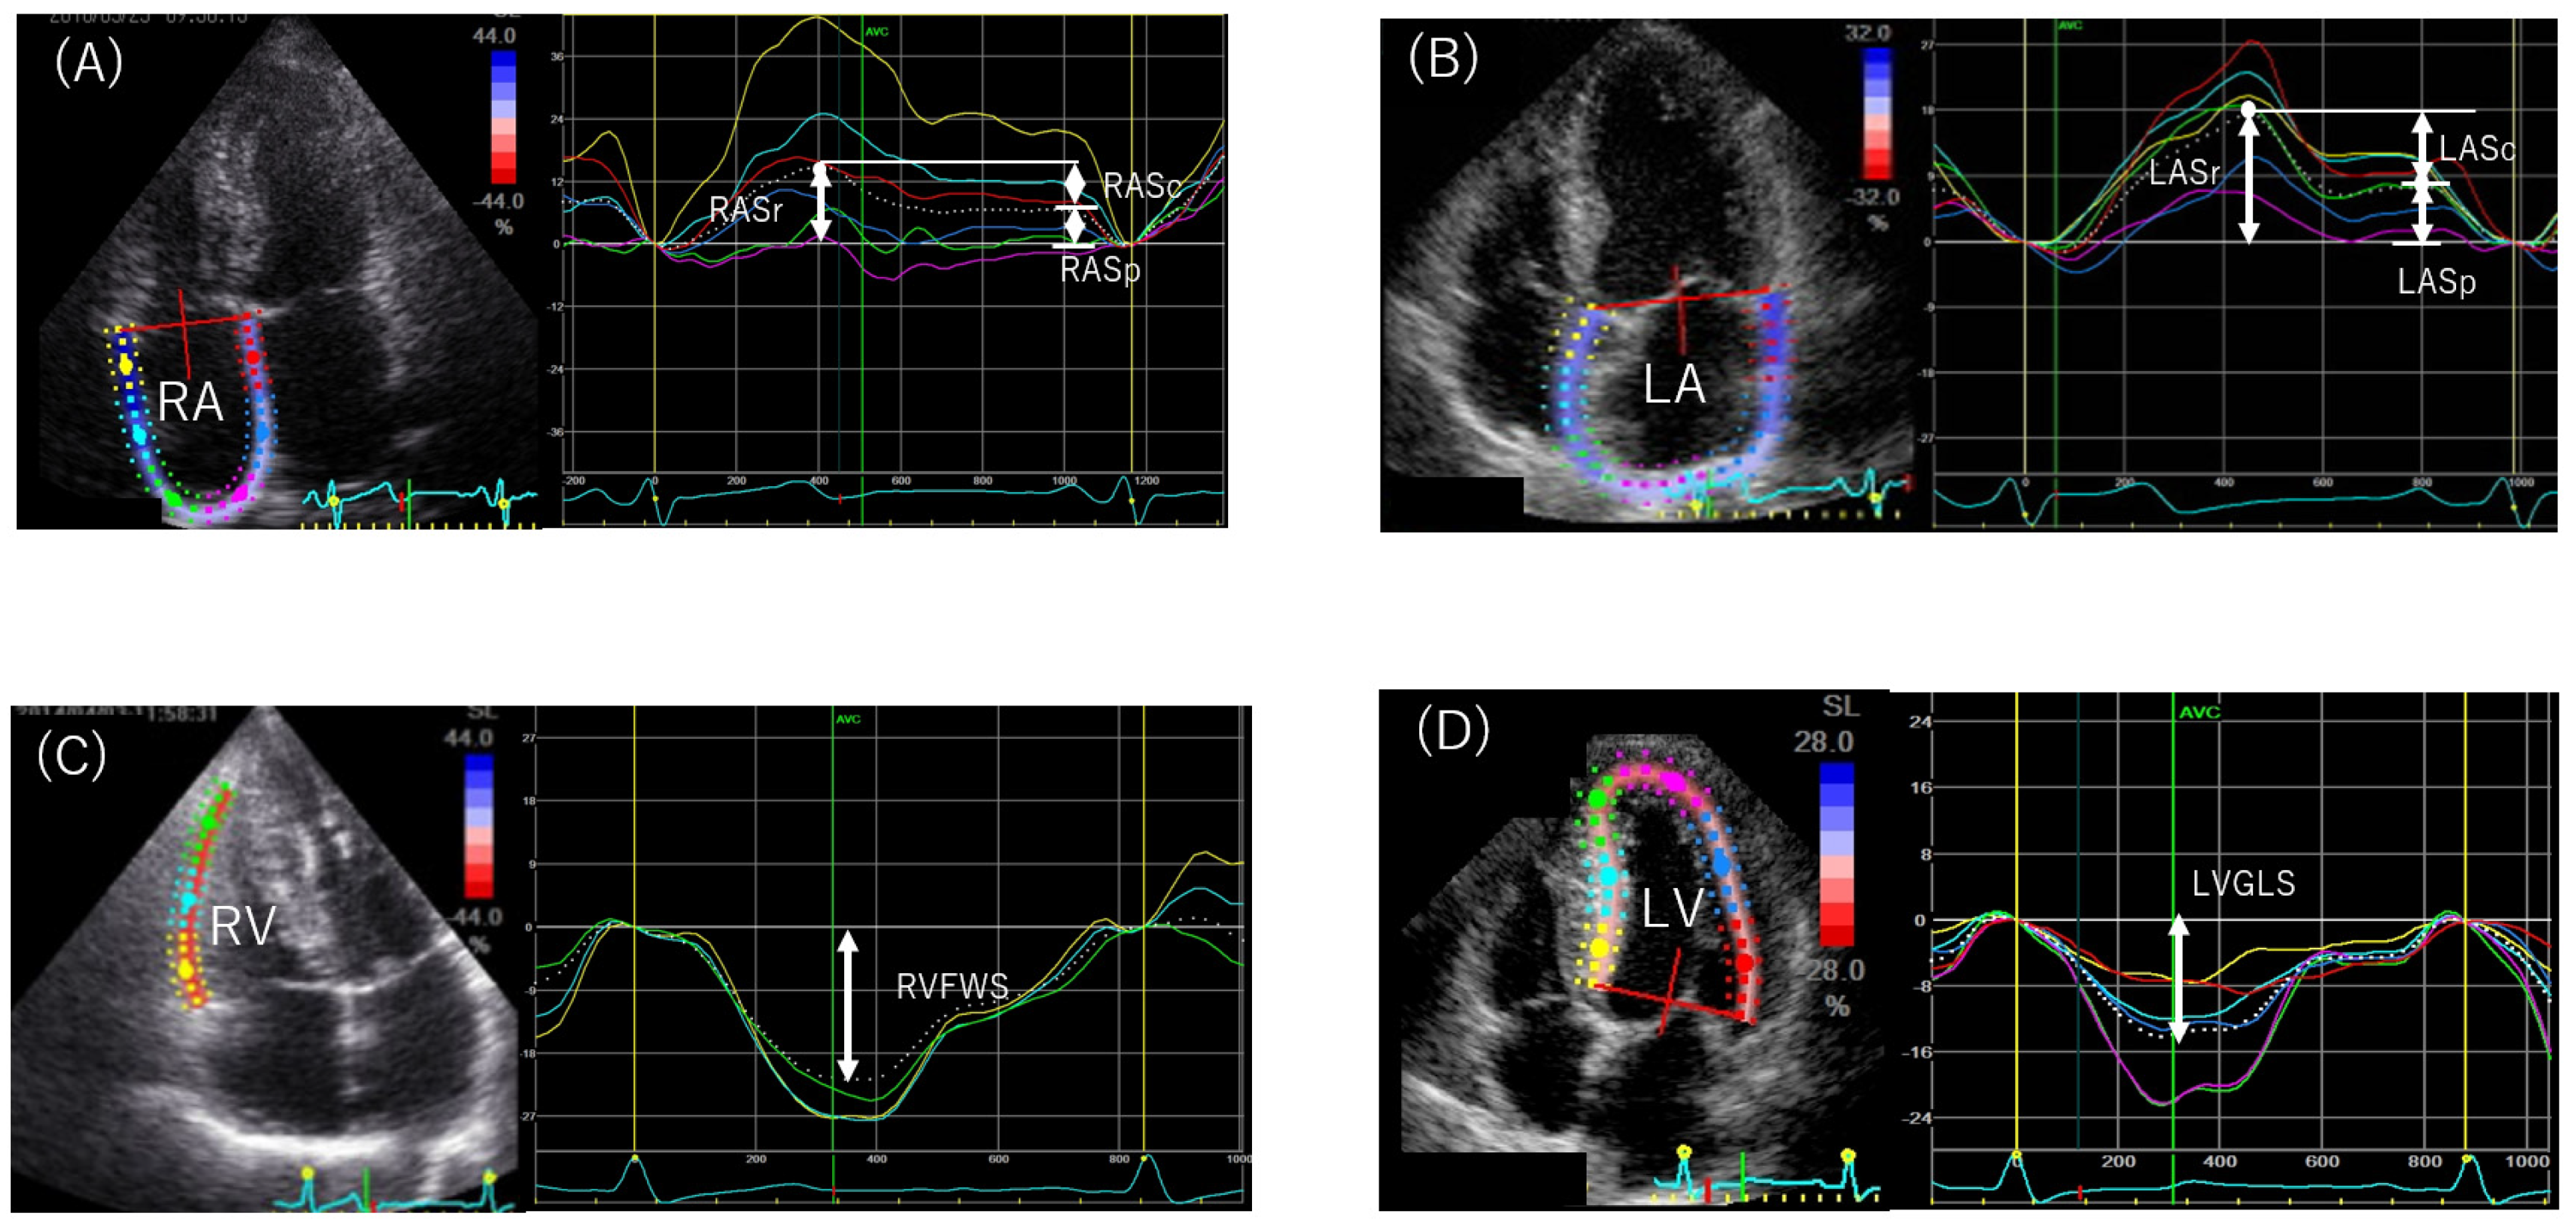

4.3.2. Speckle-Tracking Echocardiography